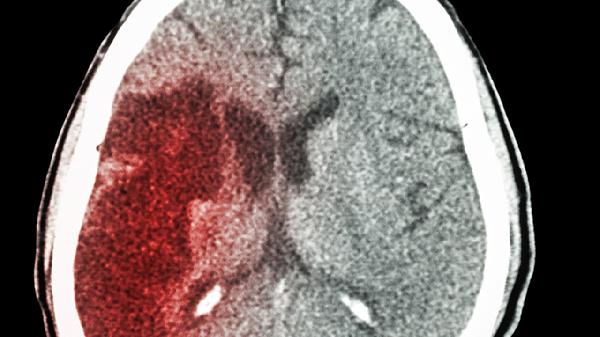

脑梗死是由于脑部血液供应障碍导致局部脑组织缺血坏死引起的疾病。脑得生丸可改善脑部血液循环,减轻脑细胞损伤,缓解因脑梗死引起的头晕、肢体麻木、语言障碍等症状。对于脑梗死后遗症患者,该药可配合康复治疗使用,有助于恢复神经功能。需在医生指导下与阿司匹林肠溶片、胞磷胆碱钠胶囊等药物联合使用。

服用脑得生丸期间应避免辛辣刺激性食物,保持低盐低脂饮食,适量进行散步等有氧运动。高血压患者需定期监测血压,糖尿病患者注意控制血糖。用药后若出现皮肤瘙痒、胃肠道不适等不良反应应及时就医。该药孕妇禁用,月经期女性慎用,不建议与其他活血类药物同时使用。脑血管疾病患者需长期规范治疗,定期复查头颅CT或核磁共振。